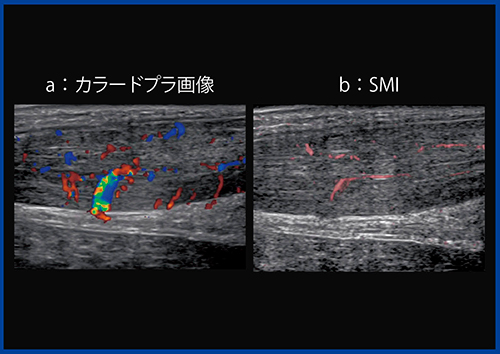

整形外科分野では,このBモードに加えてドプラ法も診断に用いてきた。図2は,受傷後1週間放置していた内返し捻挫の症例である。初診時のカラードプラ画像(図2a)では靱帯全体の血流が豊富で,強い炎症が見られたが,保存療法1週後には,腫れは残るものの血流は大きく減少し,炎症が落ち着いたことが認められる(図2b)。

ただし,腱や靱帯は,もともと血流が乏しい組織であり,強い炎症ではカラードプラで血流増加を確認できるが,炎症が弱い場合にはカラードプラでの確認は困難だった。

図2 内返し捻挫のカラードプラ画像

a:受傷後1週間放置した初診時

b:保存療法1週後

低流速の血流を描出するSMI

東芝メディカルシステムズ社が開発したSMIは,「Aplio」シリーズに搭載可能な新しいイメージング技術として,2014年1月にリリースされた。同社製超音波診断装置では,以前から血流を描出する技術として,カラードプラやパワードプラ,さらに高分解能ドプラ技術“Advanced Dynamic Flow(ADF)”を使用できたが,SMIにより,さらに微細で低流速な血流を,高い分解能で描出することが可能となった。

従来のドプラ技術では,血流以外の対象物からの不要なドプラ信号(モーションアーチファクト)に低流速の血流の信号が埋もれてしまい,低流速域での血流の描出が困難であった。SMIでは,モーションアーチファクト特有の特徴を解析し,血流信号と区別することで,血流信号のみを取り出し,低流速の血流の描出を可能にしている(図3)。

図3 低流速血流を高分解能に描出するSMI